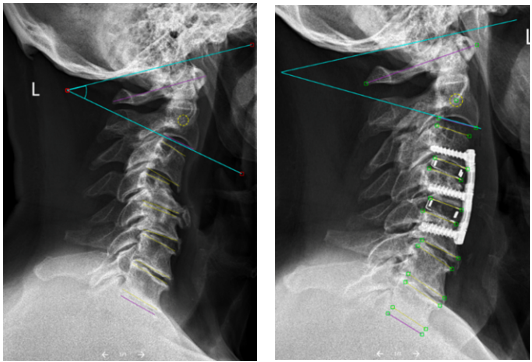

Die Studie untersuchte Röntgenbilder von Patientinnen und Patienten, die an mehreren benachbarten Stellen der Halswirbelsäule von vorne operiert wurden. Dabei entfernten die Chirurginnen und Chirurgen verschlissene Bandscheiben, korrigierten die Stellung zueinander und verschraubten die betroffenen Wirbel stabil miteinander.

Das Ergebnis ist klar: Nach dem Eingriff richtet sich der Nacken wieder natürlicher auf, und zwar nicht nur im operierten Abschnitt, sondern auch in den angrenzenden, nicht operierten Teilen der Wirbelsäule. Besonders spannend: Auch der Übergang von der Hals- zur Brustwirbelsäule wird harmonischer. Diese Zone spielt eine wichtige Rolle für Haltung und Stabilität. Wird sie entlastet, verteilt sich die Belastung günstiger und der Körper muss weniger Ausgleichsarbeit leisten.

Röntgenbild Wirbelsäule

Das Röntgenbild nach der OP (rechts) zeigt weniger Kompensationsarbeit im nicht operierten Abschnitt als vor der OP (links).